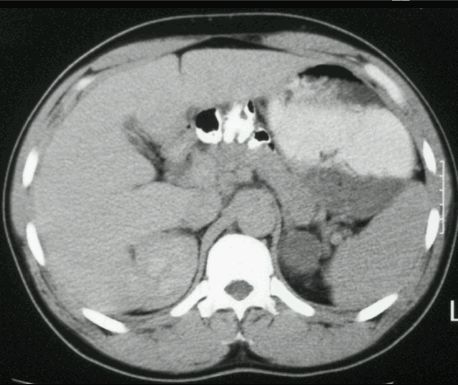

TK

GRUCZOLAK NADNERCZA